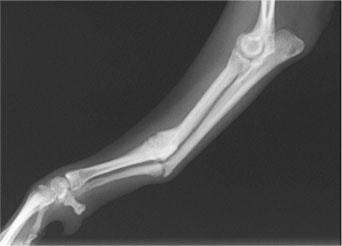

ペルシャ猫 11ヶ月齢 雄

他院にて左大腿骨遠位の成長板骨折(salter-harrisⅠ型)が認められており、治療相談を目的として来院。当院にて、キルシュナーワイヤーを用いたピンニングにより骨折部位の整復を行いました。術後の経過は良好で、現在も経過観察中です。

術前レントゲン